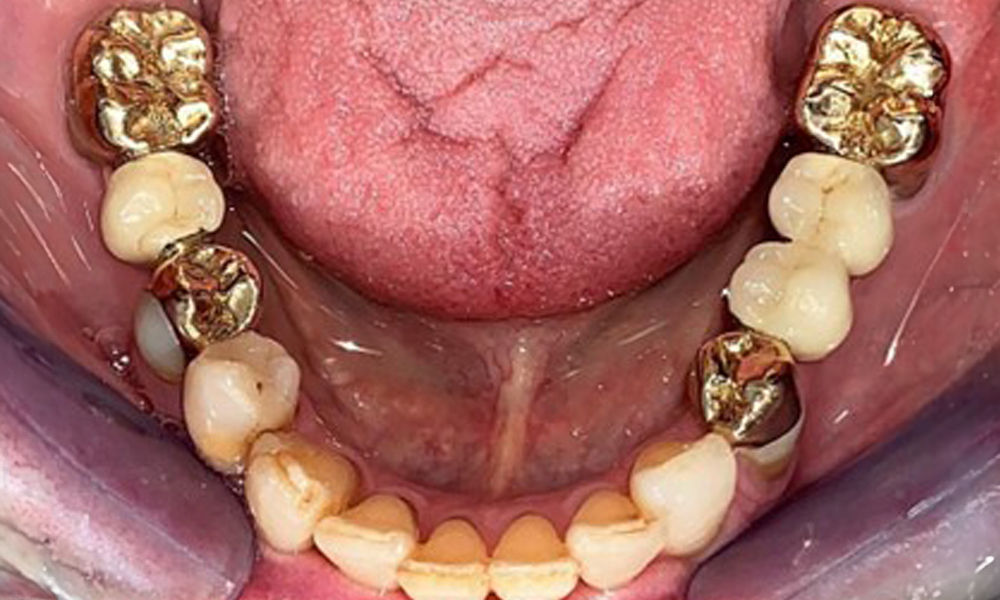

Оклузален изглед на долната челюст.

Фиг. 4: Оклузален изглед на долната челюст.

Денталните открития са следните: Комбинирани снемаеми протези на импланти и телескопични протези, поддържани от зъби, на импланти 15, 13, 21, 23, 24, 25 и зъб 11 (фиг. 1, фиг. 2, фиг. 3). Пациентът е снабден с фиксирана долночелюстна протеза. Над зъби 37-34 и 45-47 бяха налични адекватни мостове (фиг. 4), краищата на коронките бяха интактни и нямаше активен кариес. Върху зъб 43 имаше композитна пломба с маргинална празнина. Имаше рецесия на долната гингива, която разкриваше от 1 до 3 mm от кореновата повърхност. Това се отнася и за 11.